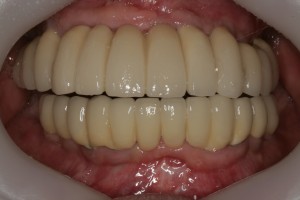

최종 보철물까지 올리고 난 후 구강 내 사진입니다.

평상시의 교합 뿐만아니라 좌우로 아래턱을 크게 움직였을 때도 불편함이 없습니다.